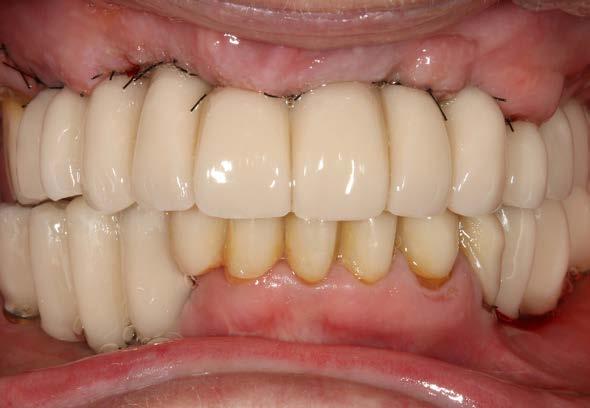

Figuras 2 y 3. Imágenes intraorales de la paciente, donde podemos observar la pérdida ósea acusada en algunos puntos con exposición de los componentes protésicos, así como transparencia incluso de las espiras de los implantes como el situado en posición 13 a través del tejido gingival.

Figura 7 y 8. Fotografías de la prótesis de carga inmediata. En ellas observamos ambas prótesis (superior e inferior) colocadas horas después de la cirugía.

Figuras 10 y 11. Caso finalizado 6 meses después, con las prótesis definitivas colocadas.